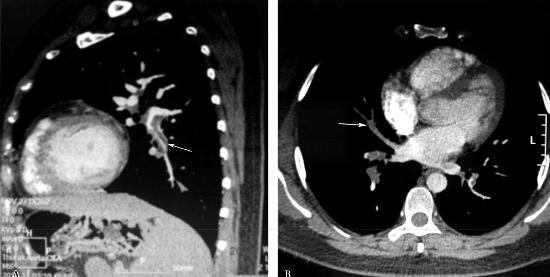

6.肺动脉CTA:双肺上叶动脉、右肺中叶动脉、双肺下叶动脉见有条片状充盈缺损,以两肺下叶为著,右肺下叶静脉密度欠均匀,其内见条状低密度影,双侧下肢深静脉见条状充盈缺损,以左下肢深静脉为著。诊断提示:双肺动脉栓塞,右肺下叶静脉栓塞,双下肢深静脉血栓(图1)。

图1

重要的检查结果有三项:①肺动脉CTA明确该患者肺动、静脉栓塞及下肢深静脉血栓形成;②心脏彩超未见异常,未见肺动脉高压;③血常规显示血小板低于正常,凝血常规显示APTT在未应用抗凝药物前即呈2倍延长。结合患者临床资料,明确该患者肺动脉、肺静脉栓塞及双下肢深静脉血栓形成的临床诊断,结合患者无血流动力学障碍及急性右心功能不全情况,治疗方案以抗凝治疗为主,但血小板及APTT异常情况可能会影响抗凝治疗的安全性。故给予安全性相对高的低分子肝素钙抗凝治疗。